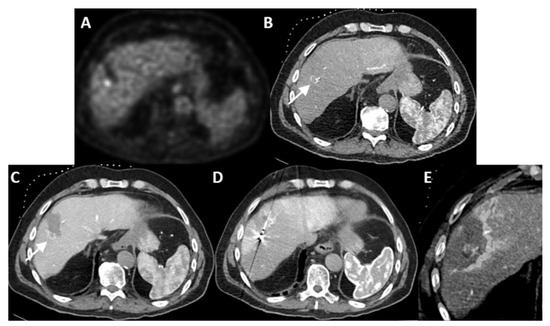

| 1 | 20 mm | Common hepatic artery | 15–20 mL Visipaque™ | Emprint™ Microwave Ablation System, Medtronic-Covidien, Boulder, CO, USA | MD Anderson, Houston, TX, USA |

| 2 | 20 and 7 mm | Common hepatic artery | 4 mL Xenetix 300® | Cool-tip™ RFA Ablation Aystem, Medtronic-Covidien, Boulder, CO, USA | Gustave Roussy, Villejuif, France |

| 3 | 12 mm | Left-sided hepatic artery | Not specified | Cool-tip™ RFA Ablation System | Gustave Roussy |

| 4 | 9 mm | Common hepatic artery | 10 mL Xenetix 300® | Emprint™ Microwave Ablation System | Amsterdam UMC, Amsterdam, The Netherlands |

| 5 | 15 mm | Coeliac trunk | 20 mL Xenetix 300® | Emprint™ Microwave Ablation System | Amsterdam UMC |

| 6 | Not applicable | Common hepatic artery | 20 mL Xenetix 300® | Emprint™ Microwave Ablation System | Amsterdam UMC |

| 7 | Confluent | Common hepatic artery | 10 mL Xenetix 300® | NanoKnife system under ECG-gating; AccuSync model 72, AngioDynamics, Latham, NY, USA | Amsterdam UMC |

| 8 | 15 mm | Common hepatic artery | 15–20 mL Visipaque™ | Emprint™ Microwave Ablation System | MD Anderson |